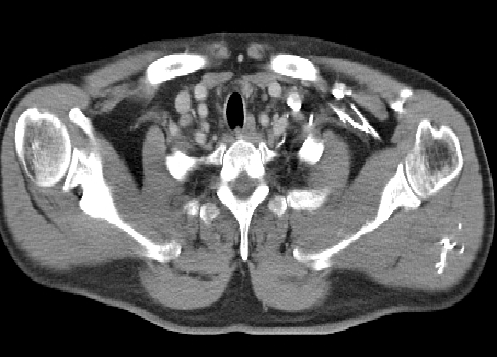

2018-07-09:

1、左残肺新见转移灶

2、左腋窝新见肿大淋巴结;余变化不大

3、脂肪肝较前明显,肝脏病灶治疗后改变较前相似

2018-09-11:左残肺转移灶稍缩小,左腋窝肿大淋巴稍缩小,余变化不大

2018-11-9:左残肺转移灶变化不大,左腋窝肿大淋巴结稍缩小

2019-03-26:左残肺转移灶增大,左腋窝肿大淋巴结相似,左锁骨上淋巴结稍大;余变化不大

2019-04-23:放疗前定位CT肺转移灶增大;余变化不大